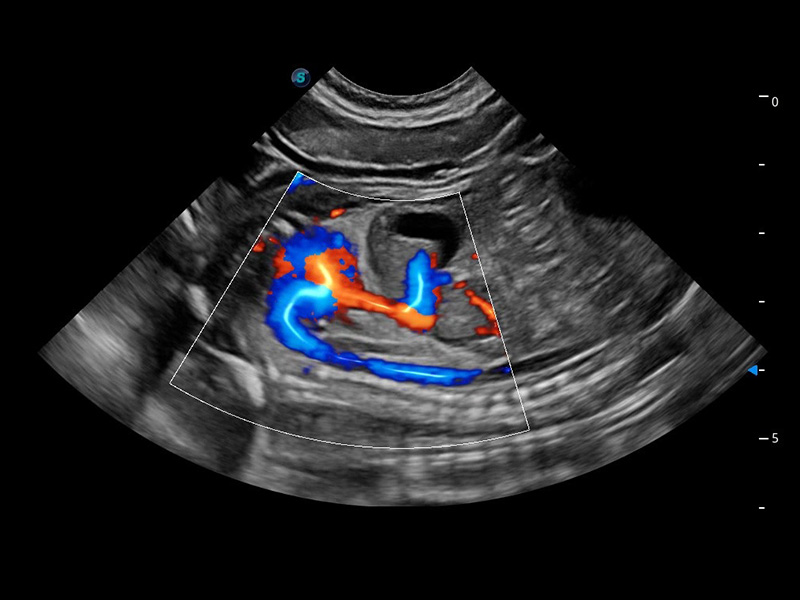

ProPet 60 作為一款高端臺式動物超聲設(shè)備,為動物醫(yī)生的日常診斷提供了一系列貼合動物臨床需求、解決臨床實際問題的高級成像功能。憑借全系列高清探頭,滿足醫(yī)生對腹部、心臟、生殖、淺表、肌骨等成像的所有需求,切實幫助您提升檢查效率,提高診斷信心。

獸用彩色多普勒超聲診斷系統(tǒng)

動物是人類最親密的朋友和最值得信賴的伙伴。開立醫(yī)療也一直致力于探索動物專用的超聲影像解決方案。 全新推出的ProPet系列,是開立在動物超聲影像智能化、專業(yè)化、精準(zhǔn)化的一次跨越式革新。動物不能用言語來表述自己的不適,通過超聲影像,ProPet系列搭建了動物醫(yī)生與不同物種溝通的“橋梁”,為動物醫(yī)生注入了“治愈之力”。